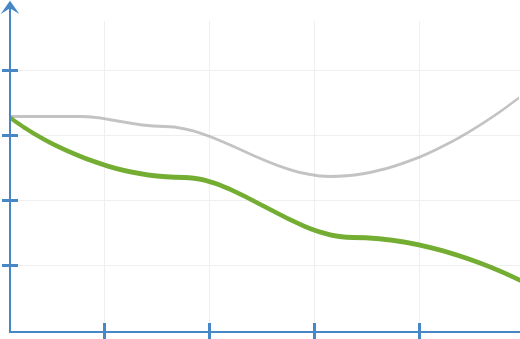

Динамика изменений

при воспалительных процессах

Без применения Prostalisan

С применением Prostalisan